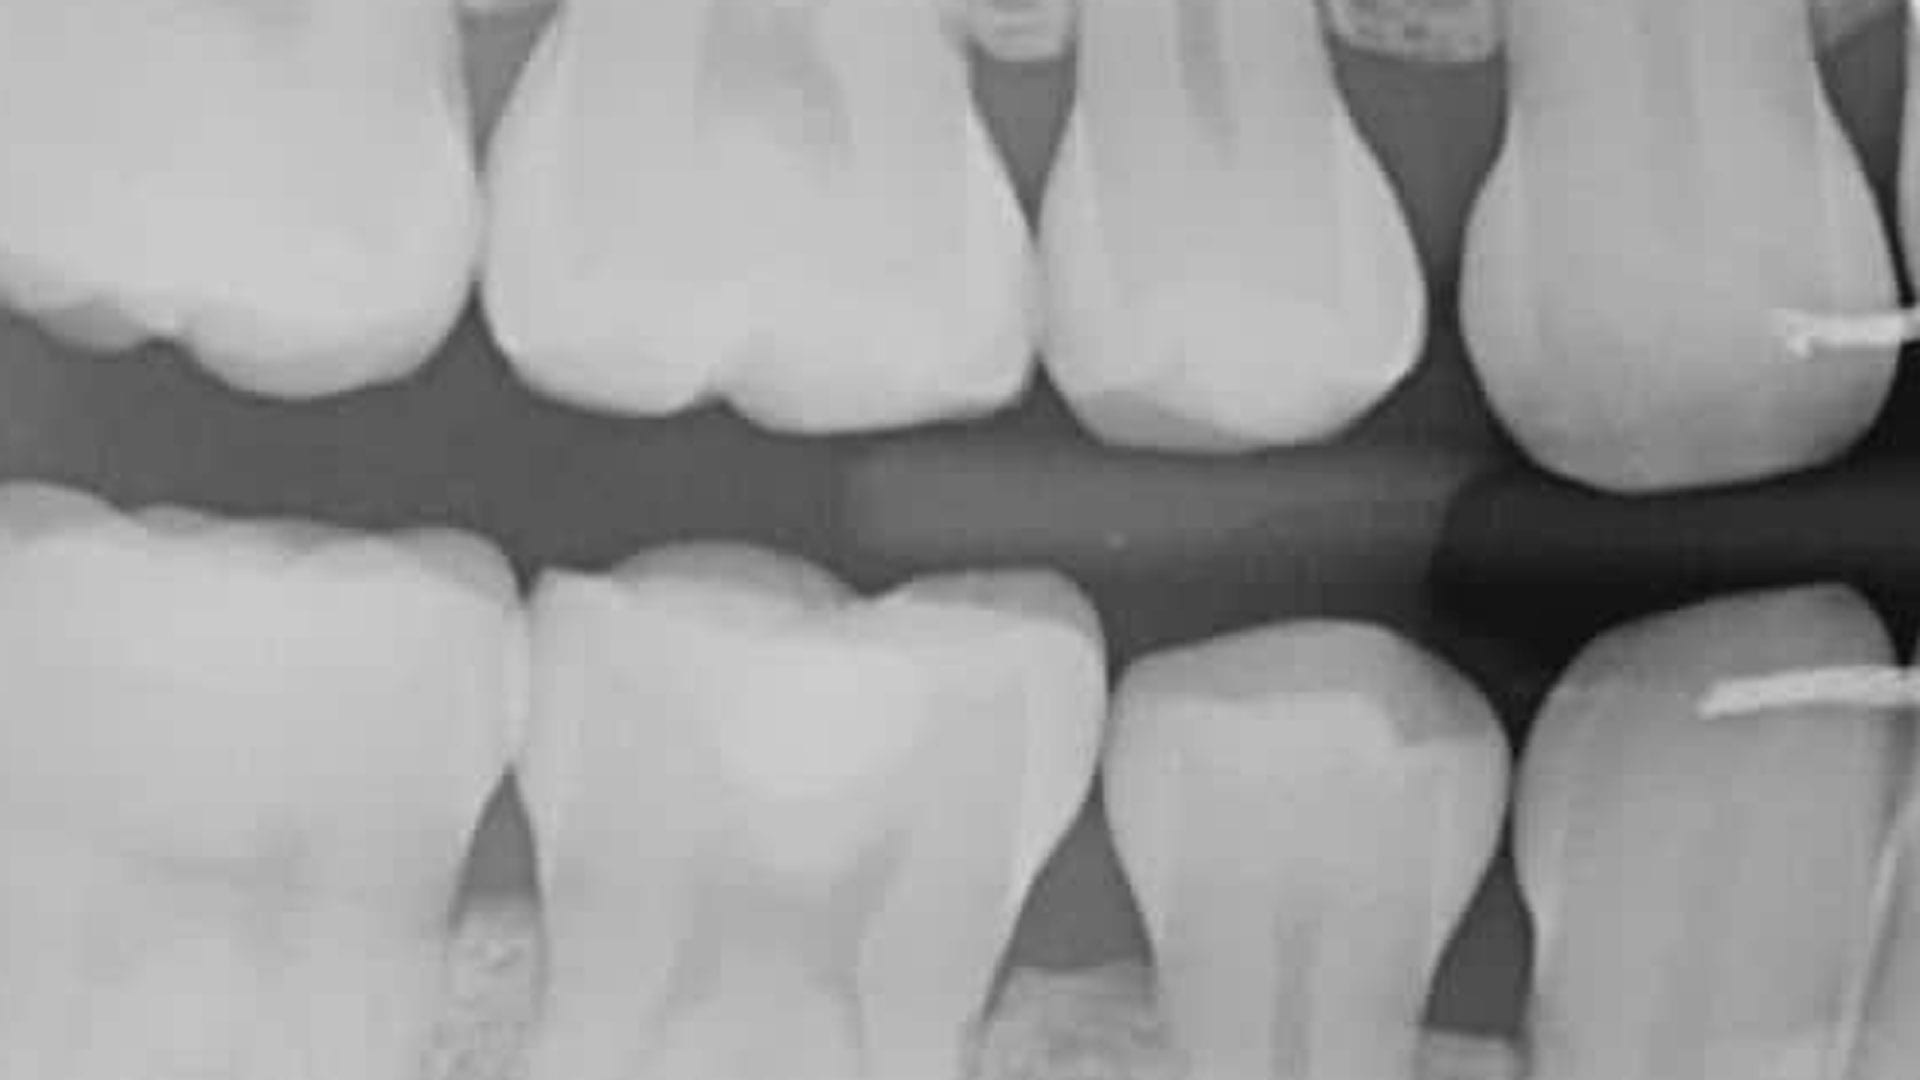

Bitewing Xray

Bitewing

This is where you bite down on a special piece of paper so your dentist can see how well the crowns of your teeth match up. It is typically used to check for cavities between teeth.